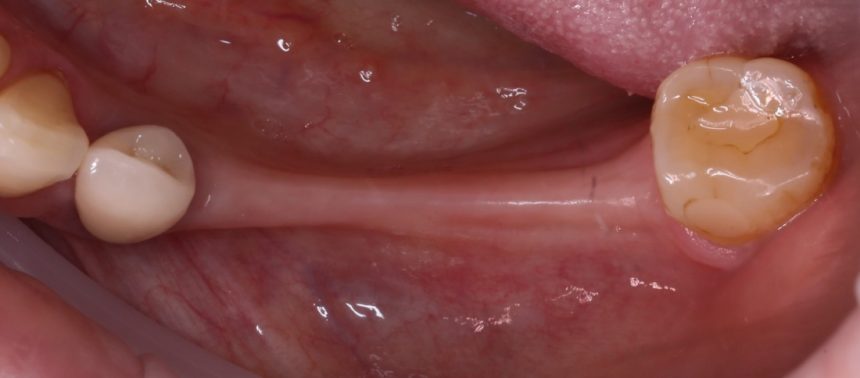

«Замковая фиксация съемного протеза» которая реализуется двумя способами: специальными шариковыми абатментами или т. н. «локаторами»:

Мы наблюдаем пациентов с подобными конструкциями больше 10 лет. Например, у лечения, описанного на картинках выше, есть продолжение:

Как видите, лечение в данном случае проходило отнюдь не гладко. Поэтому, каким бы привлекательным ни казалось использование двух имплантатов для фиксации уже существующих съемных протезов, это, всё же, временное решение, неизбежно сулящее проблемы в отдалённой перспективе.